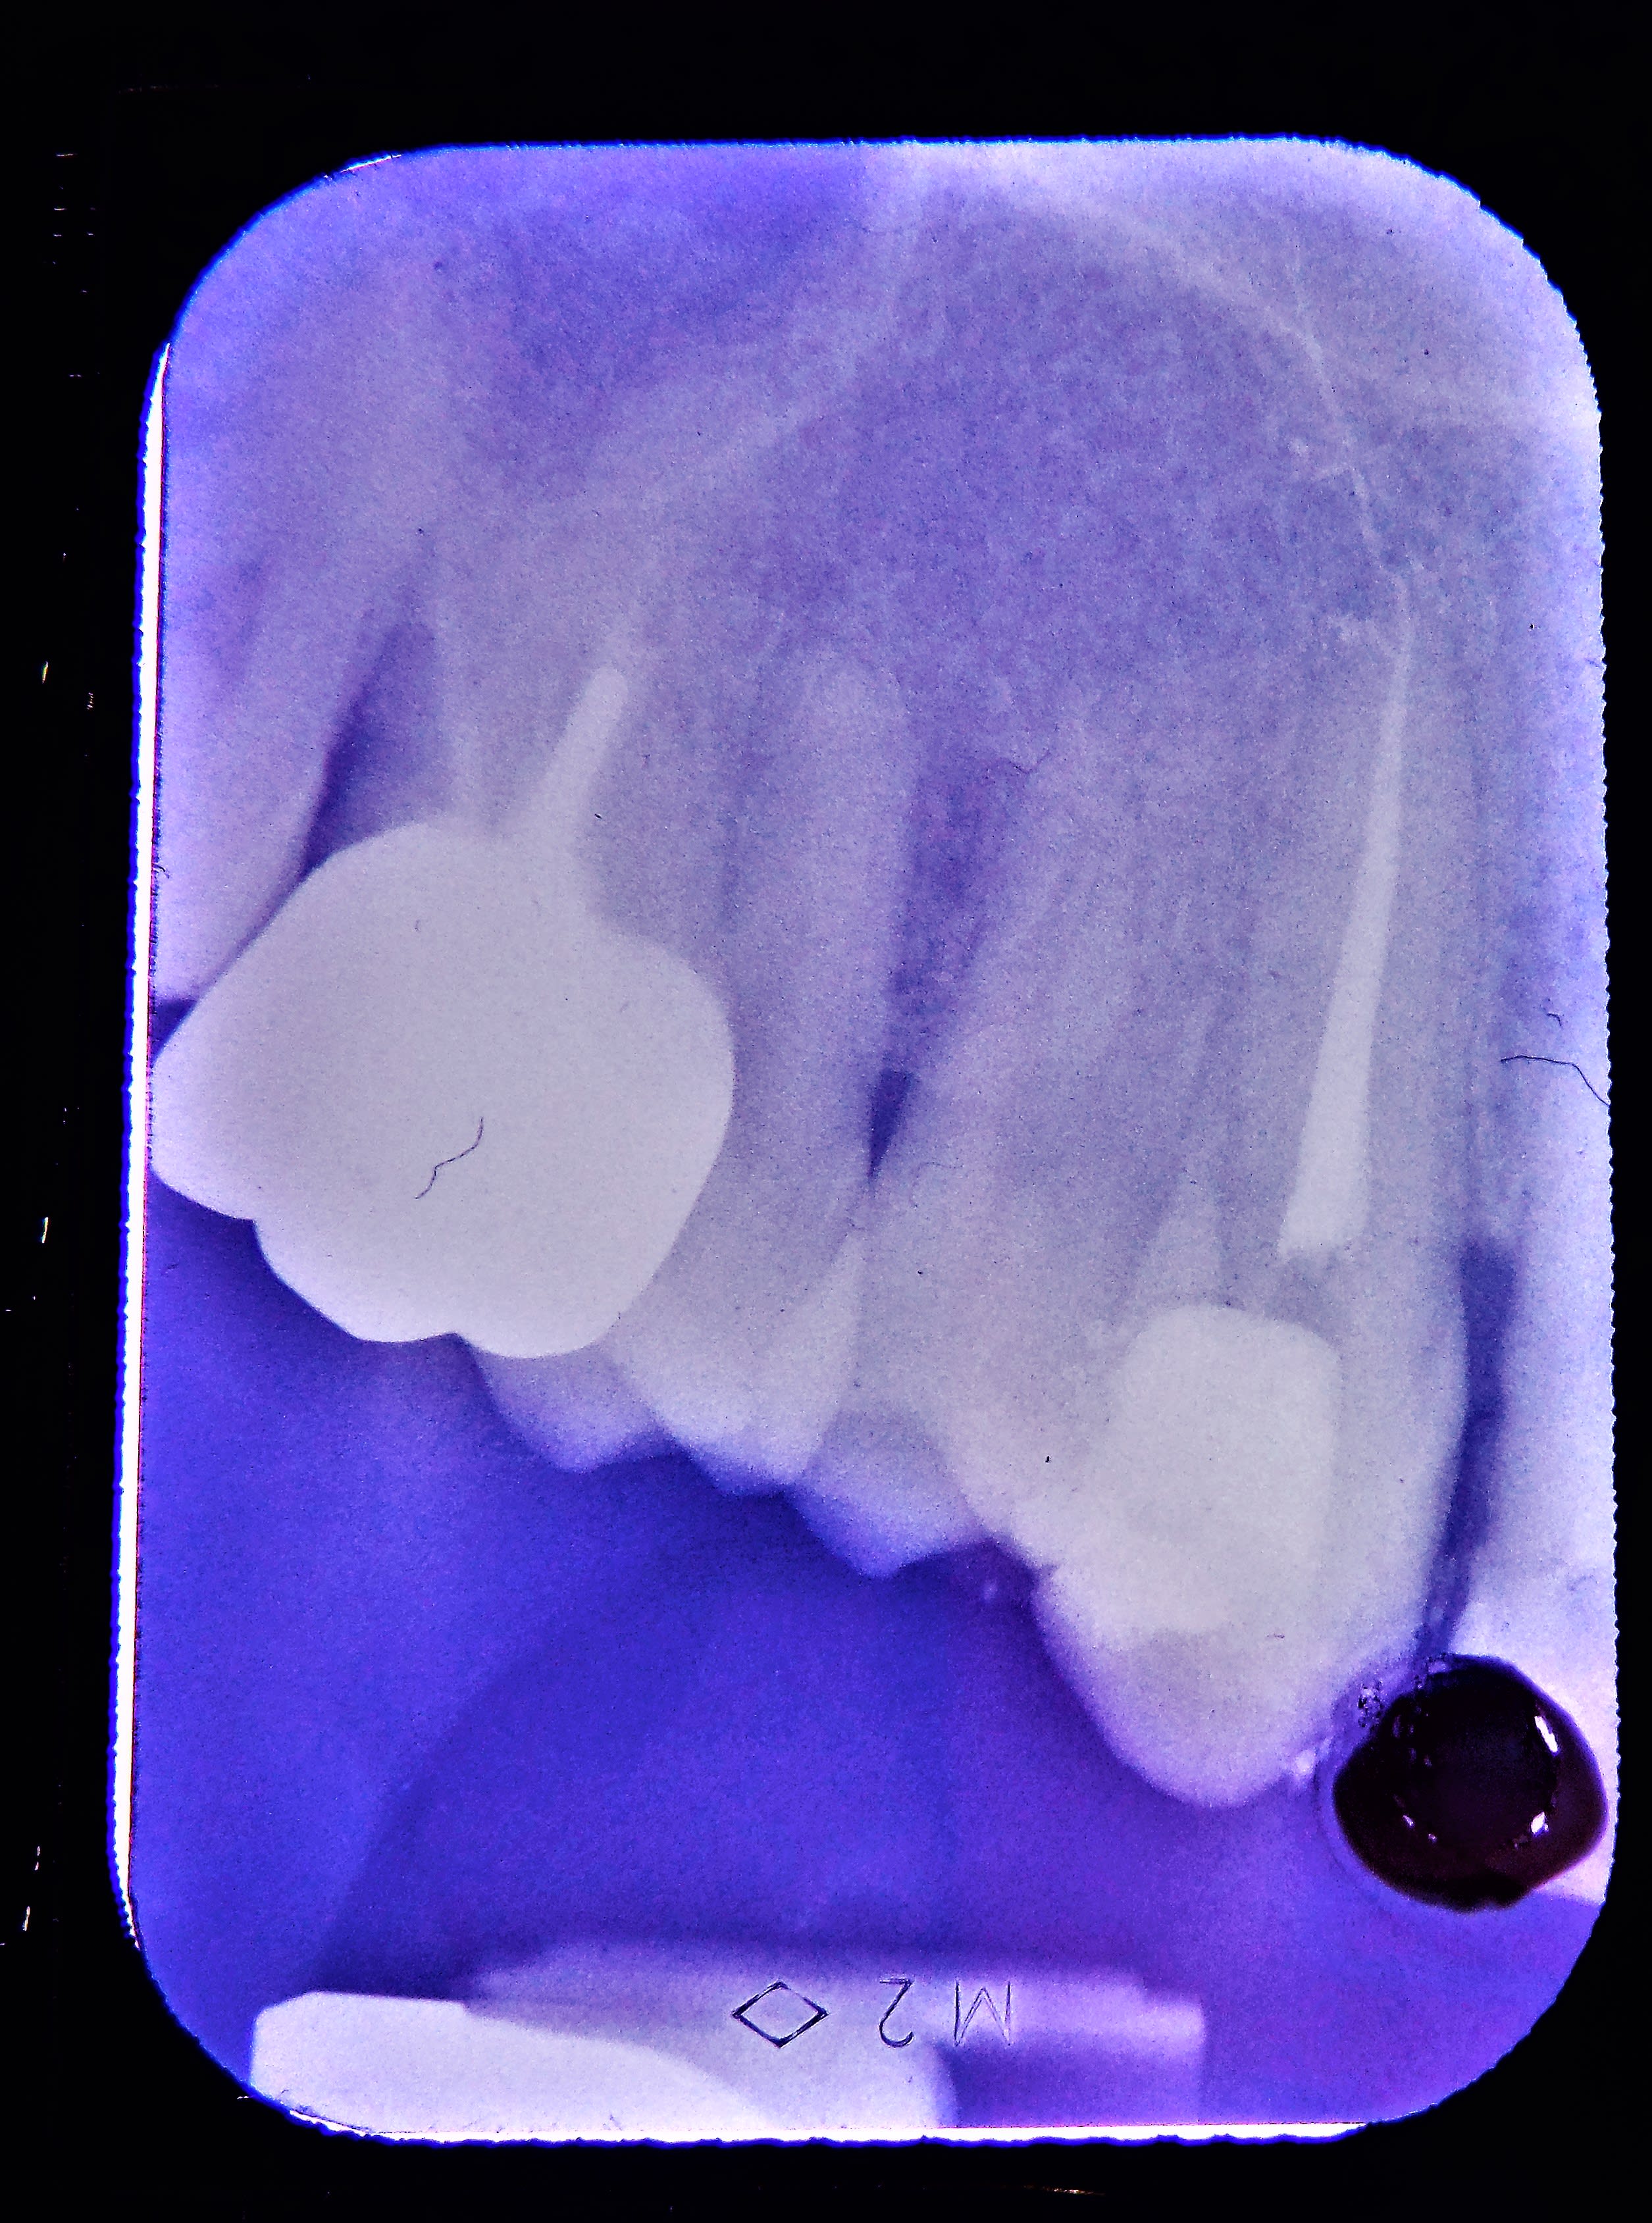

jolie fĂȘlure, qui descend jusqu'au plancher en Ml et pas en distal, je fais quoi?

Perso, reconts collée et CR sans garanti.

Moi je fais un ic coiffe sans garantie. Hasta la vista baby. -)